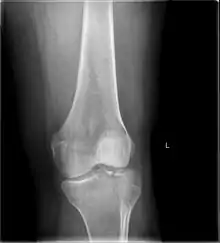

Subtle tibial plateau fracture on an AP X ray of the knee

A tibial plateau fracture seen on X-ray